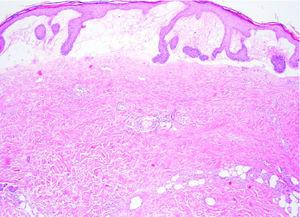

Se tomaron varias muestras para estudio histopatológico, de la espalda en el momento de la primera visita (fig. 3) y de la ampolla de la región pretibial derecha (fig. 4).

Fig. 4.--Biopsia de ampolla. Ampolla subepidérmica a expensas de marcado edema de dermis papilar; haces colágenos compactos y engrosados. (Hematoxilina-eosina, ×40.)

En la biopsia de la ampolla (fig. 4), hay un marcado edema de la dermis papilar que da lugar a la formación de una ampolla subepidérmica. En la dermis subyacente se observan infiltrados perivasculares e intersticiales constituidos por linfocitos y eosinófilos. En la dermis superficial se encuentran haces colágenos compactos y engrosados, sin objetivarse alteraciones de las fibras elásticas. No hay dilatación de vasos linfáticos. El estudio de inmunofluorescencia directa con los antisueros anti-IgG, anti-IgA, anti-IgM y anti-C3, fue negativo.